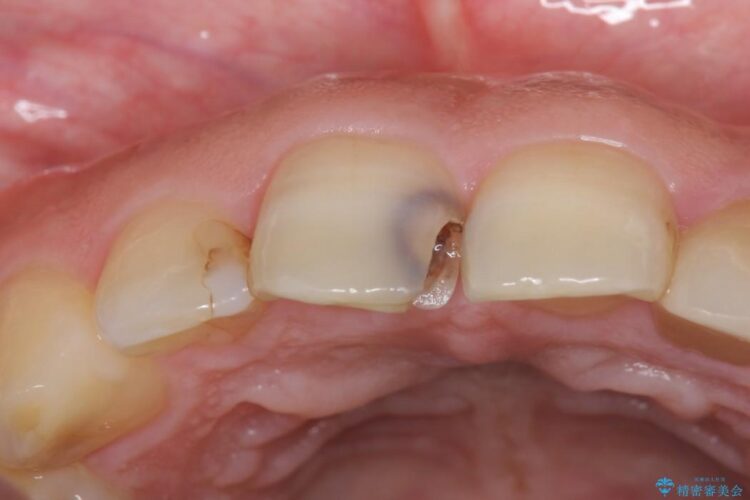

虫歯による歯の欠けと変色を主訴に来院されました。

神経に届く一歩手前の虫歯を前歯に認めました。

虫歯の範囲が大きいため詰め物ではなく、被せ物を使用した治療を行うこととしました。